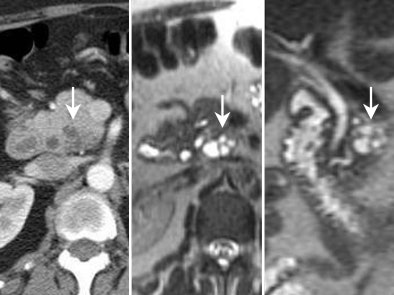

![]() |

| Typical branch-duct intraductal papillary mucinous tumor in the uncinate seen on CT (left) and on MRI cross-section (middle) and coronal view (right). |